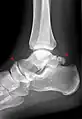

Ankle

Accessory bones of the ankle.[13]

Accessory bones at the ankle mainly include:

• Os subtibiale, with a prevalence of approximately 1%.[14] It is a secondary ossification center of the distal tibia that appears during the first year of life, and which in most people fuses with the shaft at approximately 15 years in females and approximately 17 years in males.[14]

• Os subfibulare, with a prevalence of approximately 0.2%.[15]

Os trigonum (further described below) may also be seen on an ankle X-ray.